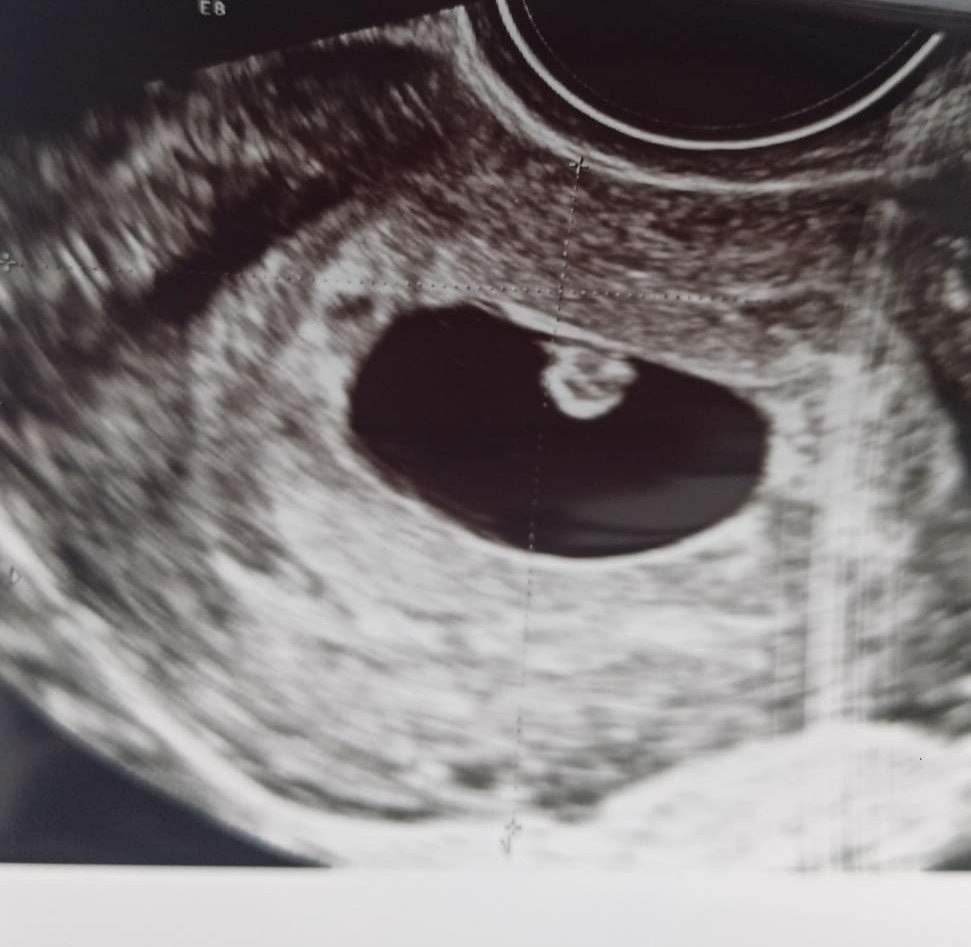

Ja byłam wczoraj prywatnie z partnerem ☺ 6t i 3d, na razie wszystko w porządku. Serce bije, fasolka 8 mm 😁

Załączniki

• IMG_20211012_162941.jpg

IMG_20211012_162941.jpg

94,8 KB · Wyświetleń: 91